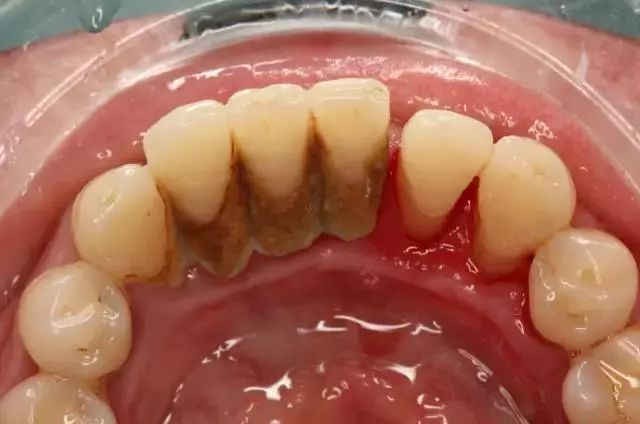

如果更严重点,有可能是这样的↓↓↓

牙龈周边积聚着大量黑褐色牙结石并伴有口腔异味,牙龈红肿明显,时间一长,很有可能造成牙齿松动脱落。

如下图↓↓↓